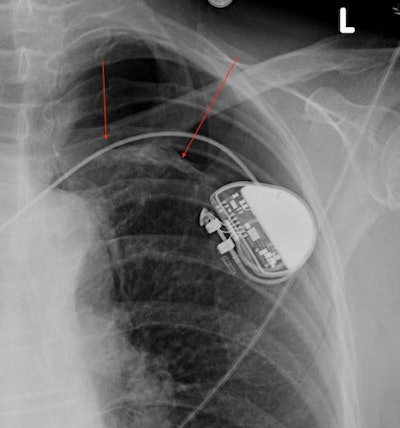

- Pneumothorax: I have always loved this bada$$-sounding name, a great name for a heavy metal band if you ask me (Google tells me that, incredibly, there is a death metal band from Belgium called Pneumothorax). A pneumothorax occupies the same potential space in the pleural cavity as a pleural effusion, but it is filled with air instead of fluid. The lungs are filled with air, so why can't you just breathe it out? The pleural cavity does not communicate with the rest of the lungs under normal conditions, and the entering air can become trapped and expand, creating our pneumothorax. On a chest x-ray, a pneumothorax tends to drift to whichever side is up, often the top of the lungs if the patient is upright. It appears as a lucency adjacent to the lung, often separated by a thin curved line representing the lung pleura. A pneumothorax can occur spontaneously (i.e., without an extrinsic cause), secondary to injury, or in the setting of a biopsy or other lung procedure.